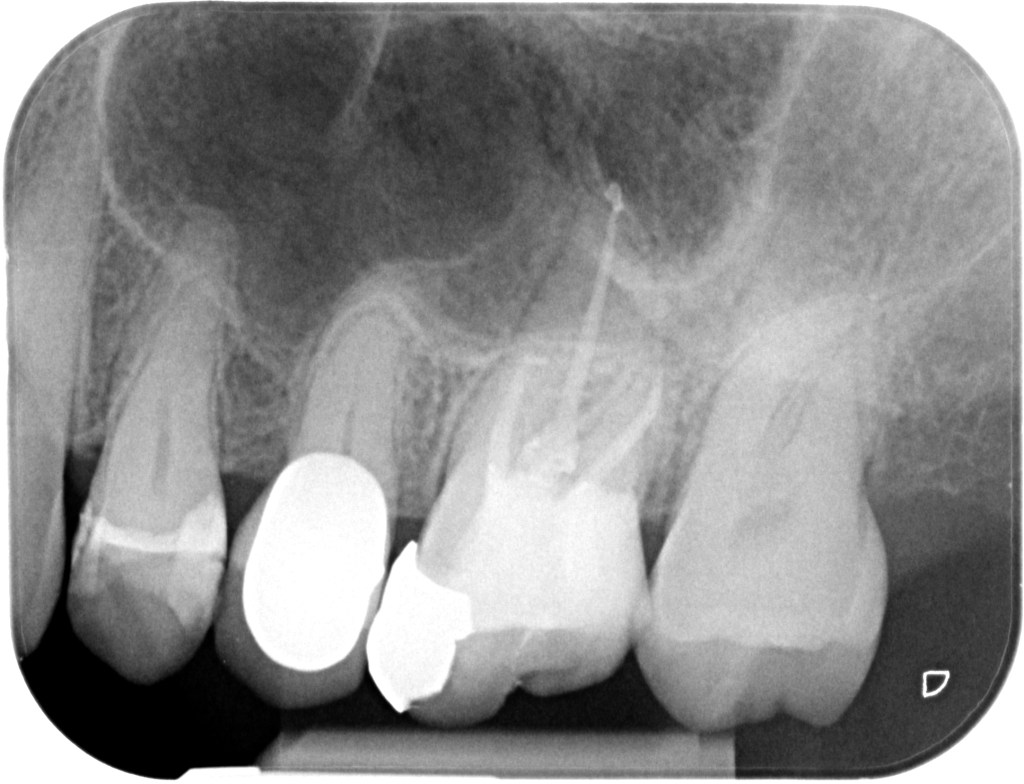

12.11.2024 Patientin ES, geb. am 21.02.1958, Zahn 26, WF- Kontrolle